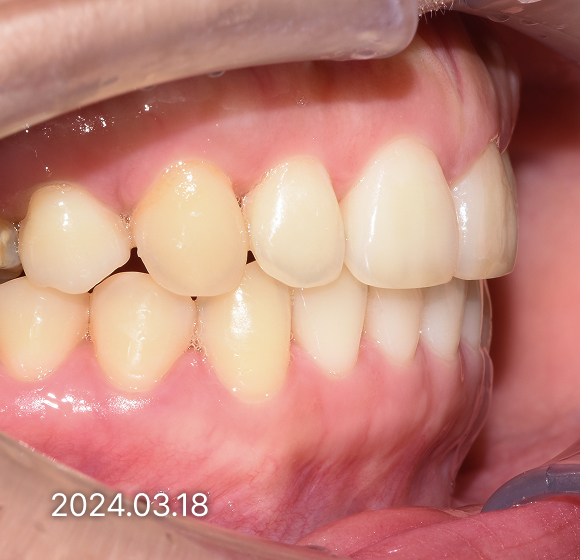

BEFORE / AFTER

전후 변화로 보는 치료사례

본 사진은 진심을담은치과교정과 치과의원에서

치료한 환자의 동일 인물 전·후 사진입니다.

개인의 구강 상태 및 관리 방법에 따라 통증 및 잇몸 염증,

턱관절 불편감 등의 부작용이 발생할 수 있습니다.

치료 전 치료 후

덧니, 삐뚤한 치열